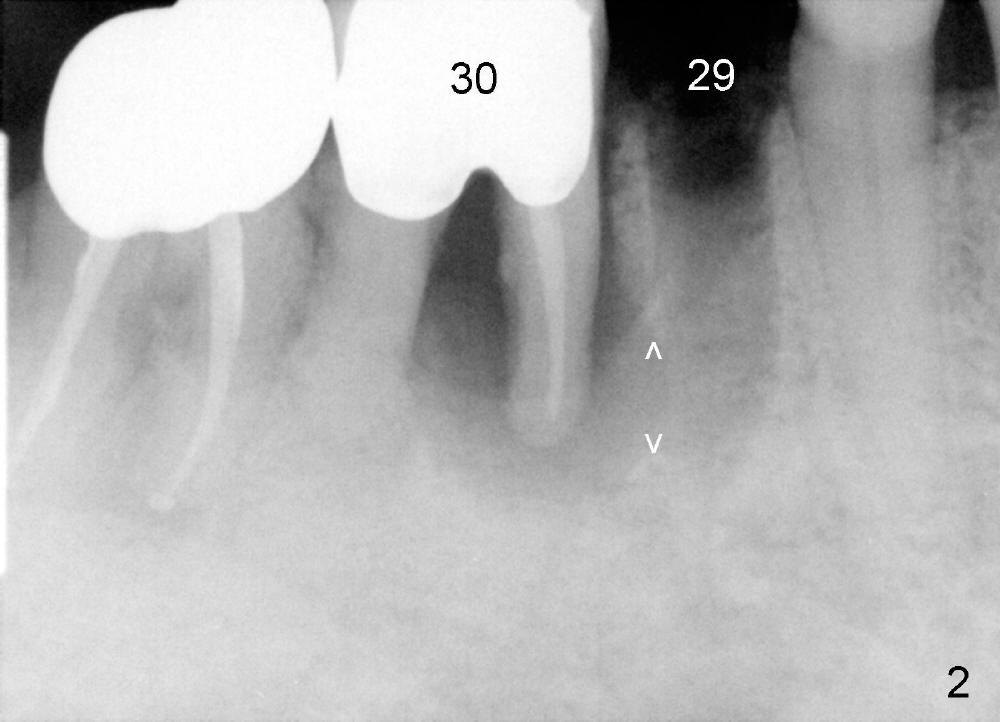

A 84-year-old man has broken the lower right 2nd bicuspid (Fig.1: #29). It is scheduled to be extracted and have an immediate implant. When the residual root is removed, the apical distal wall is too painful to be debrided. Intraop PA shows a perforation (Fig.2 between arrowheads) between the bicuspid and the 1st molar. There is large radiolucency around the mesial root of the molar. A closer look demonstrates a fistula buccal to the molar (Fig.1 <). It appears that the molar is nonsalvageable and should be replaced by an immediate implant. Due to schedule conflict, it is decided to do socket preservation first. Fig.3 reveals that the tooth #30 is extracted. Both of the sockets have been thoroughly debrided and ready for bone graft (allograft and Osteogen). The coronal portion of the bone between these teeth has undergone green stick fracture during molar extraction. Note that the buccolingual (B-L) width of these two teeth is almost identical.